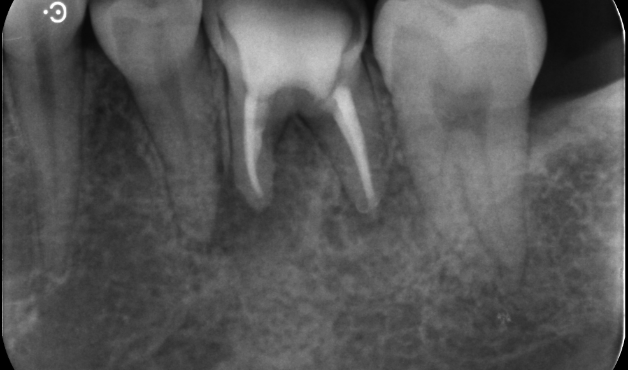

再根管治療で

歯を残した症例

タップで写真の拡大ができます。

Before

After

主訴

根管治療のやり直しをお願いされてきた

治療内容

リトリートメント(再根管治療・大臼歯)、ファイバーポストコア

治療期間

1ヶ月

治療費用

198,000

治療の

リスク

根尖部透過像が完全に消失しない可能性があります。